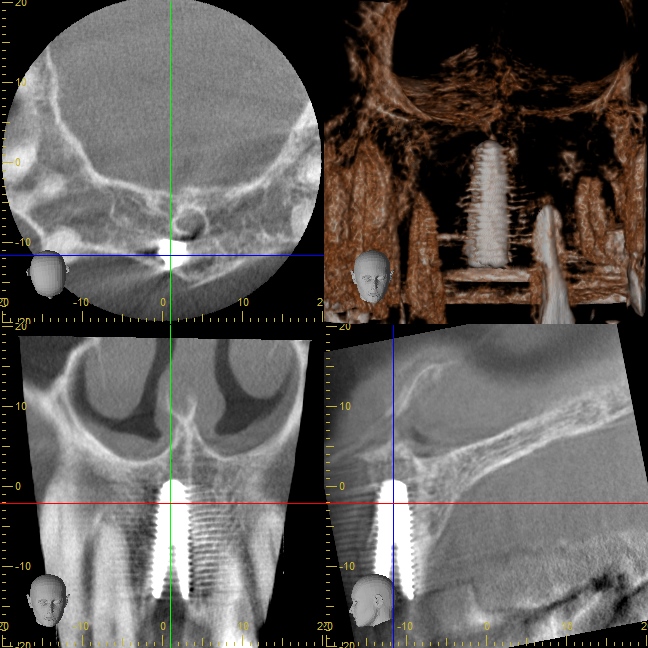

オペ前のシミュレーション

ほとんどの医院さんで

・前歯のインプラントが難しい

・骨が無いから、骨を造る処置が必要

・治療期間が1年くらい

と言われてしまう理由は、インプラントの外側(唇側)に骨が足りないことが多いからです。

今回の症例でも、右下のCT画像を見て頂くと分かるように、インプラントの外側(唇側)の骨がペラペラで薄いことが分かります。

オペ日の口腔内写真とCT

失った前歯の箇所の歯茎の骨が痩せていることが分かります。

直径4ミリほどの穴を開けていきます。

ここまでのオペ時間はわずか10分。

出血もありません。

シミュレーションと同じ位置にインプラントが埋め込まれていることが分かります。